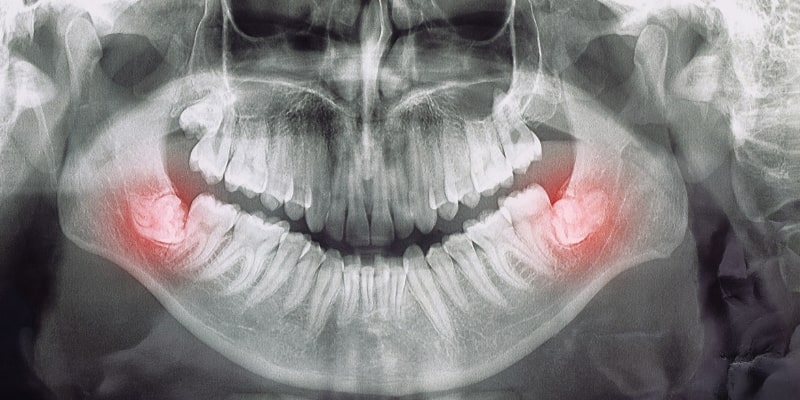

Wisdom teeth are the last set of molars that typically grow at the back of the mouth, usually between the ages of 17 and 25. While some people have no issues with their wisdom teeth, others may experience problems if there isn’t enough space for them to come through correctly.

This can lead to impacted wisdom teeth, which may grow at an angle, get stuck under the gum, or cause pain, swelling, and infection. In some cases, removal is necessary to prevent discomfort and protect surrounding teeth. Regular dental check-ups can help monitor your wisdom teeth and determine if they need treatment.

A wisdom tooth extraction may be necessary if your wisdom teeth are causing discomfort or complications. Impacted wisdom teeth, where the teeth do not have enough room to emerge properly, can lead to pain, swelling, infection, or damage to neighbouring teeth.

Other reasons for extraction include infection, cavities that are difficult to treat, or gum disease around the wisdom tooth area. If your wisdom teeth are growing at an angle or causing misalignment of your other teeth, removing them can help prevent long-term oral health issues. Regular dental check-ups can help determine if extraction is the best option for you.